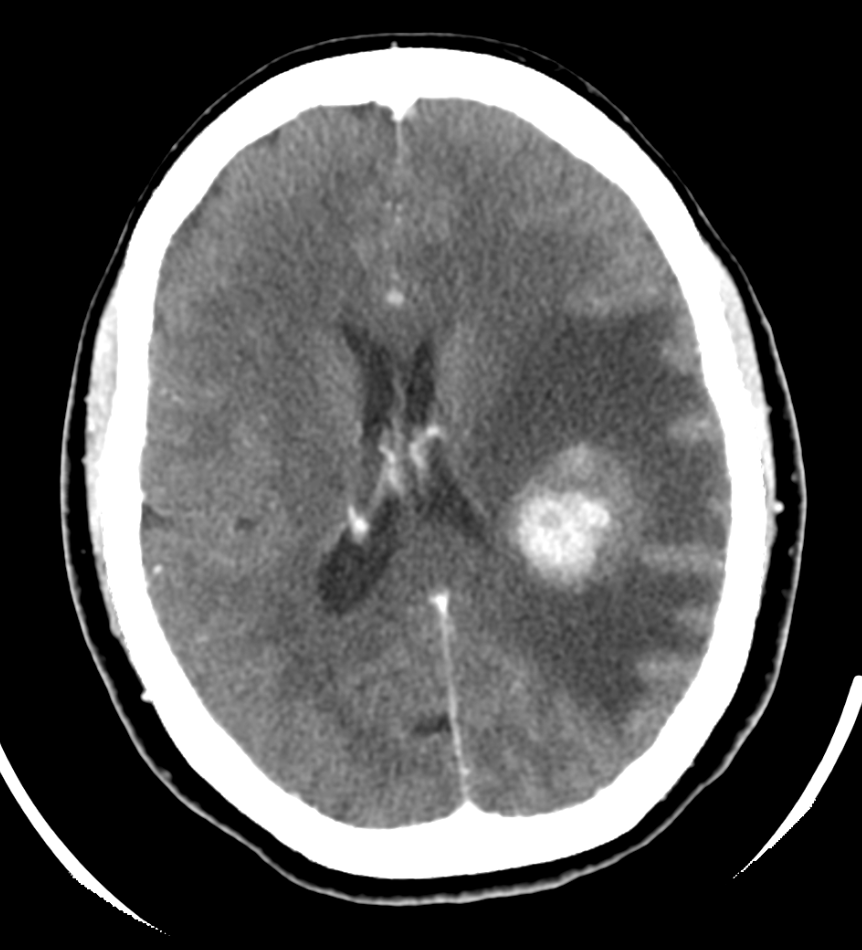

HALLAZGOS RADIOLÓGICOS